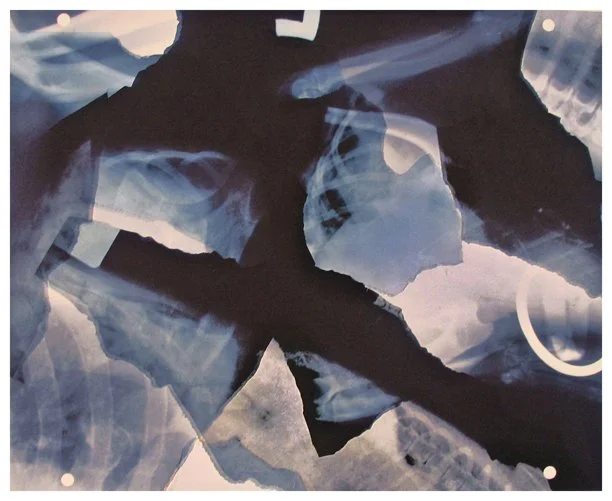

Insight is a series of collaged X-ray fragments, which were digitally composed into giclée prints. They speak not only of the body’s interior, but of the human experience it contains.

Drawn from DNA sequencing gels, mammograms, ultrasound scans, and cell cultures grown in Petri dishes, these compositions reframe diagnostic materials as metaphoric landscapes. What once served to identify illness becomes a language of line, texture, and light. They serve as a quiet meditation on fragility, resilience, and the unseen forces that shape us.

Each image in Insight is both an anatomical artifact and an artistic inquiry. Each one is part of my ongoing exploration of the relationship between Art, Science, and Medicine. Through digital layering and compositional play, I aim to dissolve the boundary between clinical detachment and emotional intimacy by inviting viewers to look inward and find meaning in the microscopic.

Ring Around a Rosey 9.75" x 9" x 4.75"